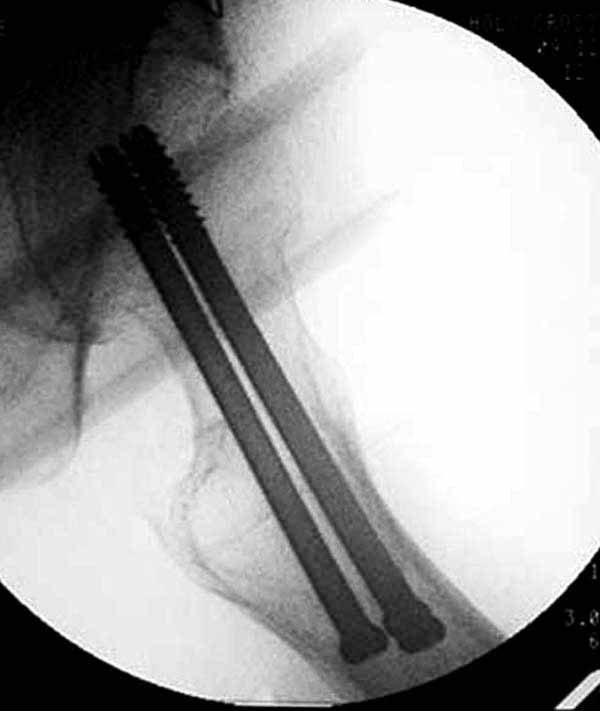

Как отметили коллеги, необходимо обратить внимание на последовательность введения каннюлированных шурупов. Рекомендуется введение в форме “V”, т.е основанием вниз, потому что в другой последовательности за счет увеличения стресса латерального кортекса имеется риск перелома. За редким исключением удается установить Guide wire с первой попытки и многоразовые пробы спицей увеличивают стресс. Небольшая травма может привести к перелому.

Работа Burstein AH and Wright TM: Fundamentals of Orthopaedic Biomechanics. Williams & Wilkins, Baltimore, pp. 160-169, 1994 доказывает, что шурупы, введенные на уровне малого вертела или ниже, приводят к осложнению. Введенные шурупы под 135 и больше градусов в 20% осложнились подвертельными переломами бедра.

Здесь подобный случай, где стрессовый перелом обнаружен через 2 недели после фиксации. Применен Blade Plate с дополнительными шурупами.